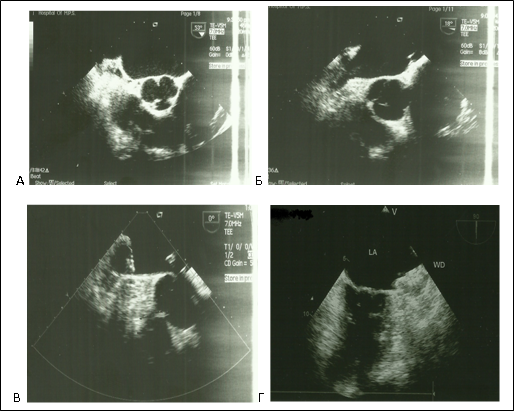

Материал и методы: с 2013 по 2015г. в Центральной клинической больнице №2 им Н.А. Семашко ОАО «РЖД», было имплантировано 15 окклюдеров «WATCHMAN» пациентам с персистирующей формой фибрилляции предсердий неревматической этиологии, поступившим для выполнения электроимпульсной терапии, электрофизиологического исследования и радиочастотной аблации, имплантации электрокардиостимулятора. Показаниями к эндоваскулярному вмешательству были угроза повторных тромбоэмболий, высокий риск кровотечений, наличие тяжелой сопутствующей соматической патологии, неэффективность консервативной антикоагулянтной терапии. Из исследования исключались пациенты со стенозом левого атриовентрикулярного отверстия, тромбами в ушке левого предсердия. На дооперационном этапе всем пациентам выполнялась стандартная трансторакальная эхокардиография и чреспищеводная эхокардиография, для оценки анатомии ушка левого предсердия, определения его размеров в четырех проекциях, а также взаимоотношение ушка левого предсердия и левой верхней легочной вены. Для оценки риска инсульта и тромбоэмболических событий использовалась шкала CHA2DS2 и ее новая модификация CHA2DS2-VASc. Перед выпиской из стационара всем оперированным больным проводилась контрольная чреспищеводная эхокардиография, которую повторяли в послеоперационном периоде через 1.5, 6 и 12 месяцев.

Результаты: средний возраст больных составил 52 года. Всем пациентам процедура имплантации окклюдера «WATCHMAN» проведена успешно. Вмешательства выполнялись без использования общего наркоза, под местной анестезией. Средняя продолжительность операции составила 42±11,3мин. На каждого пациента было использовано по одному устройству. Смены окклюдера в связи с неверным определением размера или другими причинами не было. У 5 пациентов (анатомическая форма ушка «chicken wing») под углами 90 — 135° интраоперационно выявлена протрузия нижнего края окклюдера до 1/3 длины. У пациентов с имплантированным в УЛП окклюдерами 33 и 27 размерами, по нижнему краю регистрировался резидуальный поток диаметром 5мм и 2 мм соответственно. Осложнений во время операции, так и в ближайшем послеоперационном периоде не зарегистрировано. Через 12 месяцев наблюдения изменений положения окклюдера и наличие тромбов на поверхности окклюдера и в УЛП ни у одного пациента не зарегистрировано. Не отмечено дислокации, эмболизации, изменения положения устройств. Диаметр резидуального потока по нижнему краю импланта 33 размера у одного пациента через 6 месяцев уменьшился с 5 мм до 2 мм, у другого остался прежним – 2 мм. Ни у одного пациента не были зафиксированы эпизоды нарушения мозгового кровообращения, а также другие тромбоэмболические события.